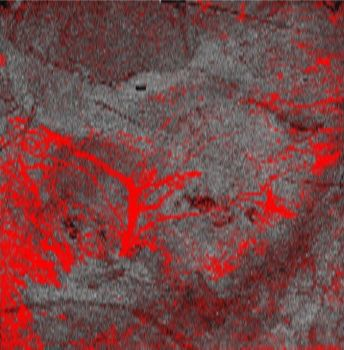

A dynamic OCT image of advanced melanoma taken with the VivoSight scanner is shown; the blood vessel pattern has changed and now shows large, distorted blood vessels. (Photo credit: PRNewsfoto/Michelson Diagnostics)

"Cancers grow their own blood vessel network to supply oxygen and nutrients," explains Nathalie de Carvalho of the University of Modena and Reggio Emilia and the study's lead author. "We analyzed the shapes of the vessels in the OCT images of melanomas and correlated the frequency of different shapes with the Breslow depths (the thickness of the tumors, measured from biopsy samples). We found that certain vessel shapes appeared much more frequently in thicker tumors. The vessels grown by the tumor seem to grow more chaotically and become more malformed as the cancer progresses."

"Our goal with this work is to help develop a faster, more-efficient, and less-invasive diagnostic and treatment pathway for melanoma," says Julia Welzel of General Hospital Augsburg. "Patients with advanced disease should get aggressive treatment as quickly as possible--also, those with early-stage melanomas should not have to undergo expensive invasive sentinel lymph node biopsy operations if their melanoma is reliably confirmed as very low-risk. We believe dynamic OCT imaging could help with these goals and the results of this study are very encouraging. The next stage of our work is to analyze the link between vessel shapes and the actual degree of metastasis of the melanomas in a larger cohort, and not just the Breslow depth."